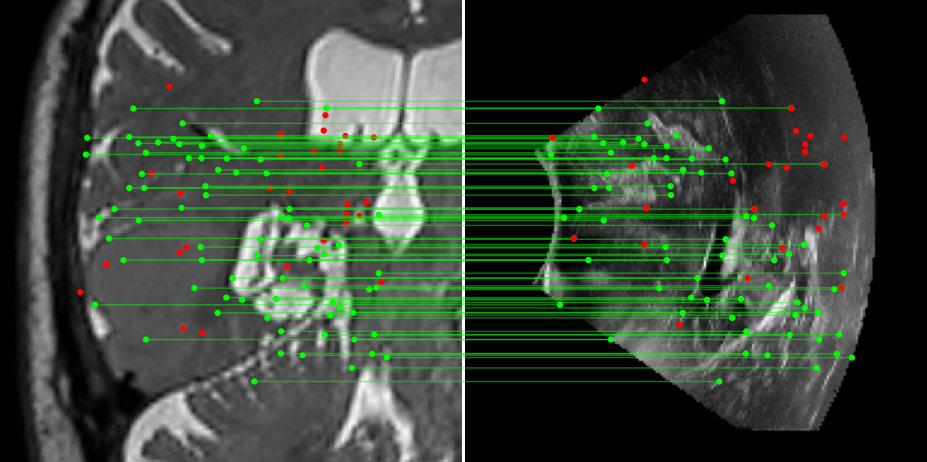

Figure 3: Examples of matching on three cases, one per column (MR on left and US on right). From top to bottom: SIFT+Cosine, MIND+Cosine, SP+Cosine, SP+LG, Ours+LG, Ours+Cosine. Correct matches recovered by each method are shown in green lines and mismatched are shown with a red dot.

To evaluate the performance of our model against existing image methods, we compared it to three approaches: SIFT [16], which remains the standard for keypoints matching, SuperPoint (SP) [3] built using a self-supervised learning approach and MIND [10], a modality-invariant descriptor for medical imaging, that although not designed for 1-to-1 keypoint matching, is extensively used for multimodal medical image registration through grid regularizing. We use SIFT and SP as keypoints detectors and descriptors, while we combine MIND with SP keypoints since it only provides a descriptor. We match these descriptors using both Cosine similarity and the deep neural network LightGlue (LG) [15] when possible (SP and Ours). Results reported in Table 2 and shown in Fig. 3 show that our approach outperforms these methods in terms of matching score, precision, and number of matched points. We only report results on three cases for readability reasons. Associating our descriptor with Cosine and LG reached similar performance depending on the metric.